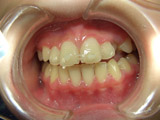

2番目の写真はH20 1月です。

だんだん2番目の歯が前に出てきて並んできました。